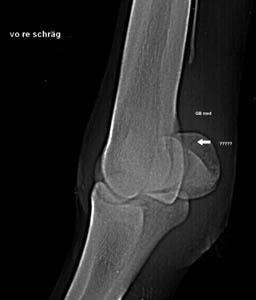

Maligner Knochentumor (Osteosarkom) beim Hund. Rechtes Vorderbein unauffällig, linkes Vorderbein zeigt die tumorbedingte Auftreibung in der Elle vor dem Handgelenk. Unterstützend kann hier die Homöopathie helfen. Amputation und Chemotherapie wird empfohlen. In diesem Fall Therapie der entzündungsbedingten Schmerzen unter Berücksichtigung des Tumors. Die Begleitung der Hundebesitzer ist eine wichtige Aufgabe des Homöopathen, oft kann ein trauriges Ende nicht abgewendet werden. Heilungsversprechen sind absolut unethisch!